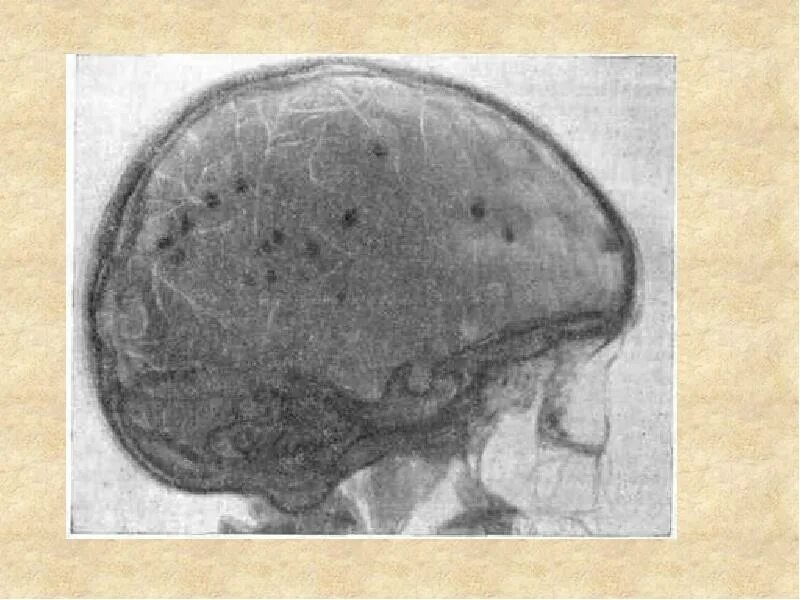

Туберкулезный склероз